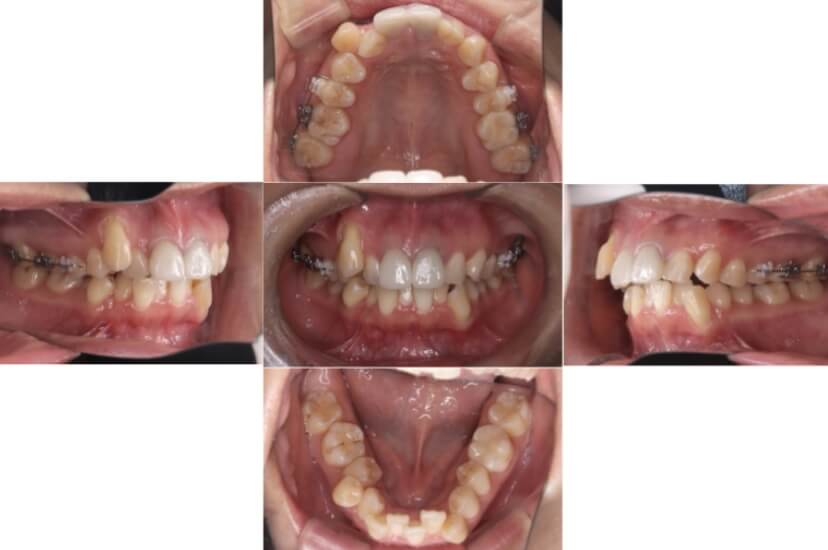

症例2

上下顎前突、叢生

抜歯

ブラケット矯正

上下顎前突、叢生(上下出っ歯、上下の前歯のガタガタ)のケースです。

装置はラビアル(上下表側)で、上下顎の小臼歯を4本抜歯を行っています。抜歯したスペースを使って、上下の前歯の後方移動と叢生(ガタガタ)の改善を行っています。

主訴 前歯のガタガタと口元がでているのが気になる。

年齢・性別 30歳 女性

お住まいの地域 東京都大田区

治療方針 抜歯スペースを利用して上前歯の叢生(ガタガタ)と口元突出の改善

抜歯部位 上下顎左右第一小臼歯

使用装置 ラビアル(上下表側)、顎間ゴム

治療期間 1年11か月

治療回数 13回

リテーナー クリアリテーナー

BEFORE

AFTER